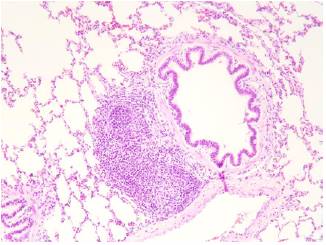

En el cerdo se encontró un sistema de conducción, transición e intercambio, así como bronquios, bronquiolos, alvéolos, trama vascular y distribución de neumocitos de tipo 1 y de tipo 2, similares a los de los humanos. Además, se observó tejido linfoide hiperplásico asociado a las paredes bronquiales (Bronchus-Associated Lymphoid Tissue, BALT), el cual solo se observa en enfermedades respiratorias como la bronquiolitis folicular en los humanos (figura 4).